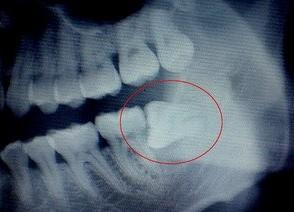

广州牙科介绍,有的智齿在没有萌出完全埋在了牙槽骨内横着长,又叫水平阻生智齿,是比较麻烦的一种智齿,那么,智齿横着长怎么办呢?

说道:智齿横着长,可能会挤压前面的牙齿,严重时可能会使一排牙齿显得排列不齐,影响到咀嚼功能。此外,智齿阻生与前牙之间形成食物残渣或细菌的积累,易形成龋齿、冠周炎,而一旦产生冠周炎,反复发作。对此建议,为了有效避免智齿阻生带来的危害,一定要尽早及时的拔除阻生的智齿。